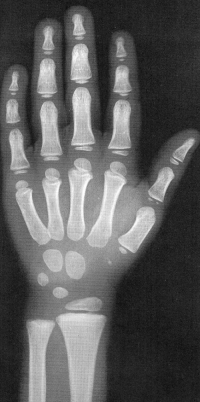

Sexo Feminino

5 anos

5 anos e 9 meses